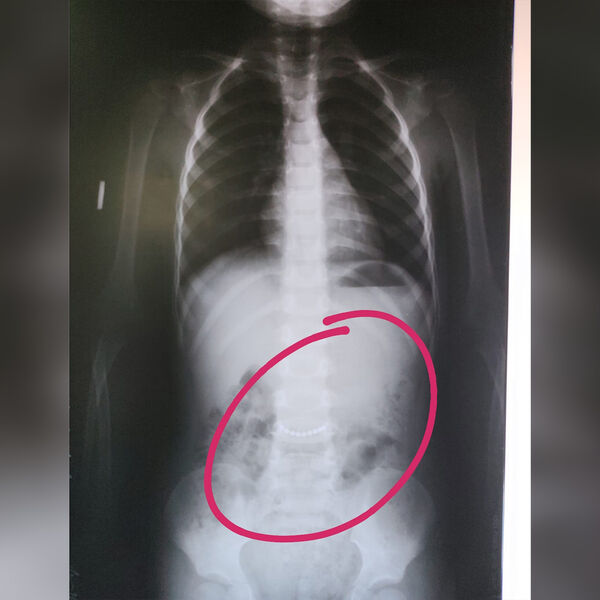

В Раевскую центральную районную больницу был доставлен трехлетний ребенок с подозрением на инородное тело в брюшной полости, выяснилось, что мальчик проглотил цепочку. Об этом сообщает пресс-служба медицинского учреждения.

При каких обстоятельствах трехлетний мальчик проглотил инородное тело, медики не уточнили. В ходе обследования в брюшной полости ребенка врачи обнаружили проглоченную им металлическую цепочку длиной несколько сантиметров.